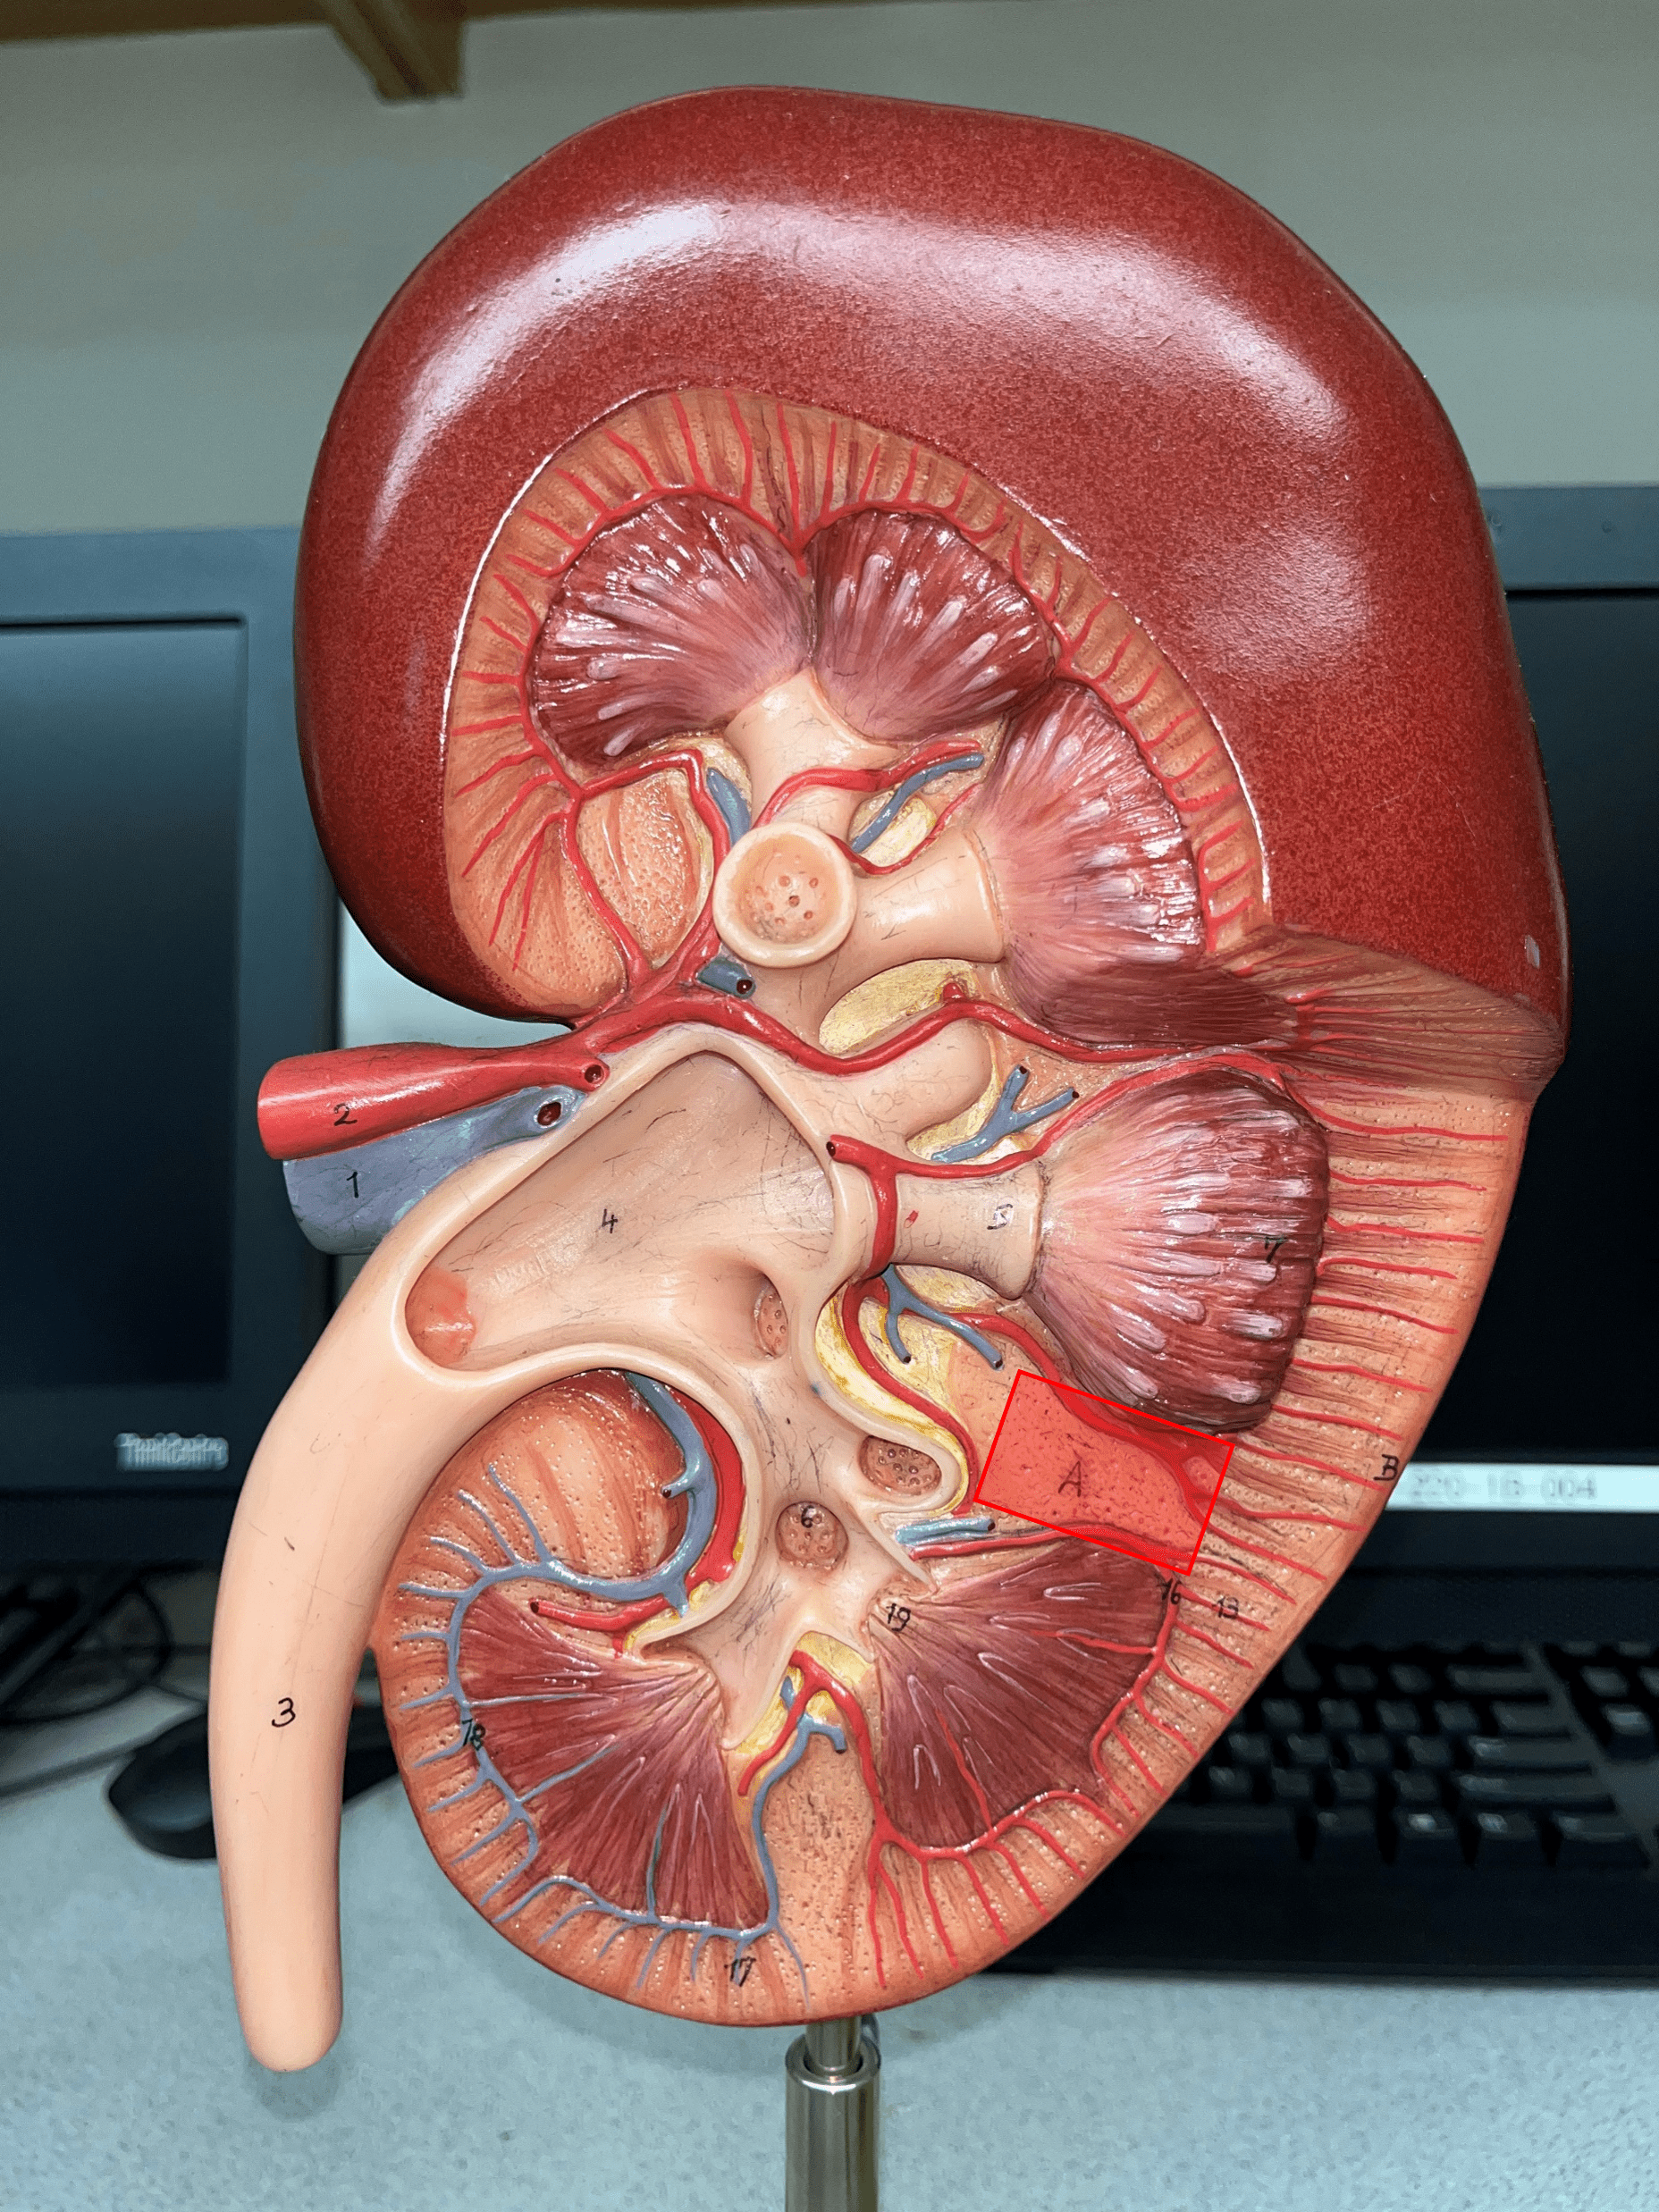

renal cortex

• The outermost region of the internal kidney.

• Superficial to the renal medulla.

• Appears slightly granular.

• Superficial to the renal medulla.

• Appears slightly granular.